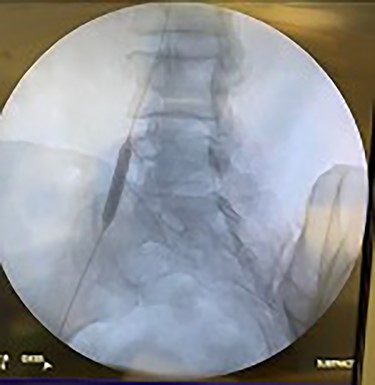

Catheter arteriogram results showed significant occlusion of the left iliac artery (Figs 3 and 4), the right iliac artery (Fig. 1), as well as the distal abdominal aorta (Fig. 2). There were numerous collateral vessels noted, indicating the presence of long-standing proximal stenosis (Fig. 1). The decision was made to use angioplasty to help widen the areas of stenosis. An 8 mm × 40 mm Passeo balloon was advanced from the right femoral artery into the left iliac artery (Fig. 7) and insufflated to 6 mmHg (Fig. 6). The balloon was allowed to remain expanded for 1 min and then was deflated. Next, the distal aorta was repaired in a similar fashion. The balloon was advanced into the distal aorta from the right femoral access and insufflated to 12 mmHg (Fig. 8). The balloon was allowed to remain expanded for 90 s.

Fluoroscopy of bilateral iliac arteries showing significant arterial disease.